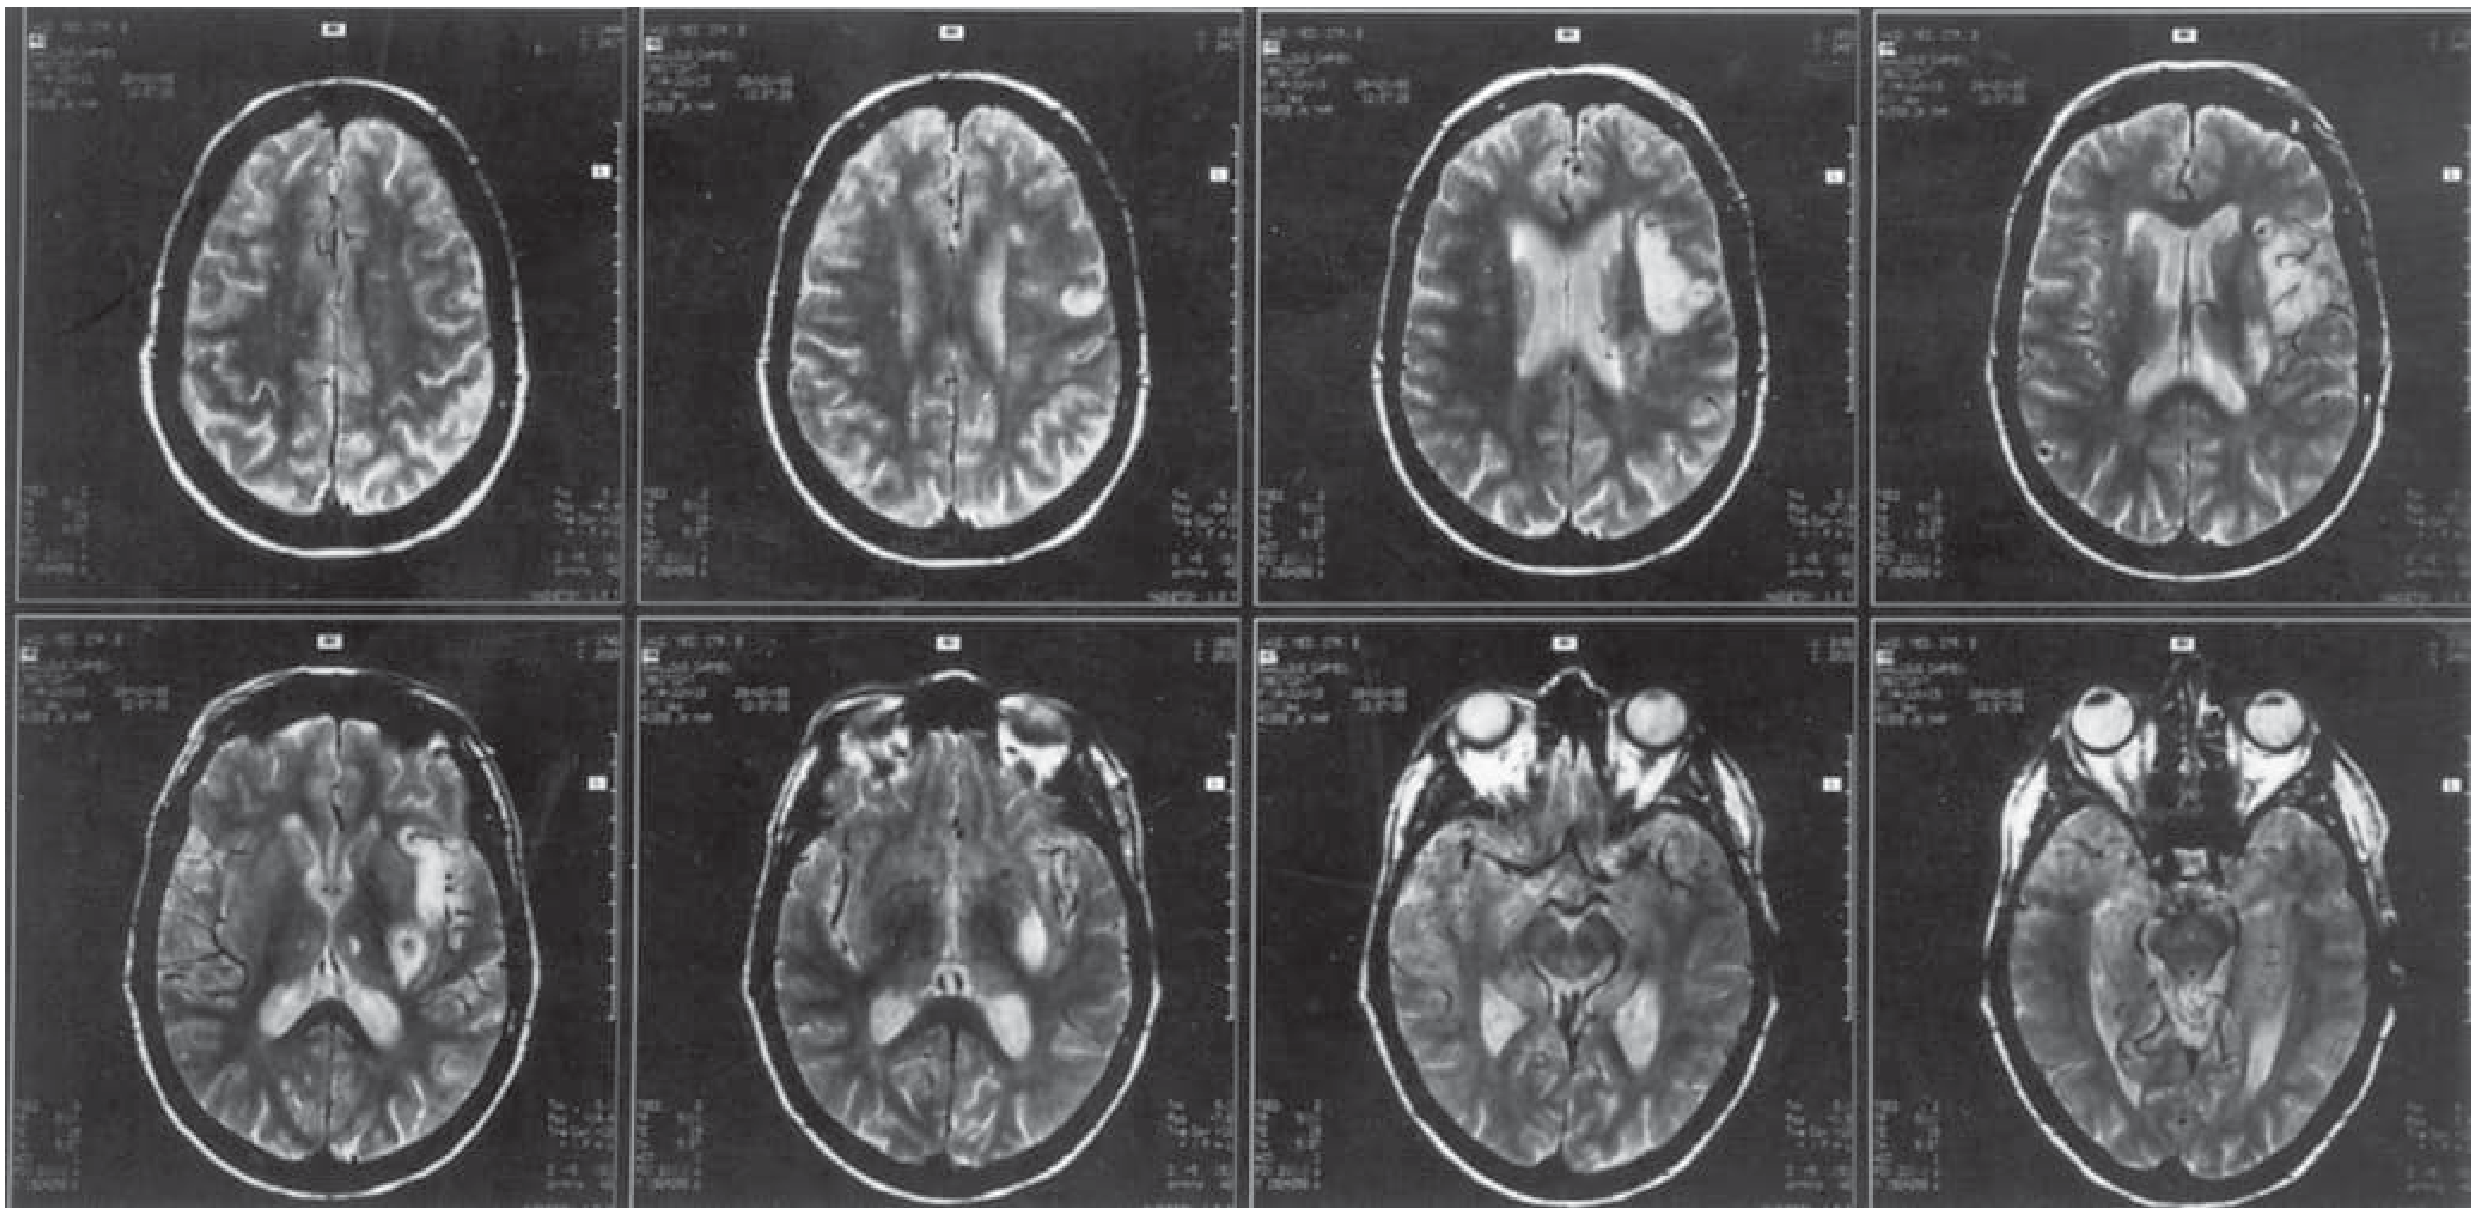

MRI of Wernicke's aphasia showing large left superior temporal lobe lesion

Axial and coronal MRI of an elderly woman with Wernicke's aphasia showing a large left superior temporal lobe lesion — Bradley and Daroff's Neurology in Clinical Practice, p. 209